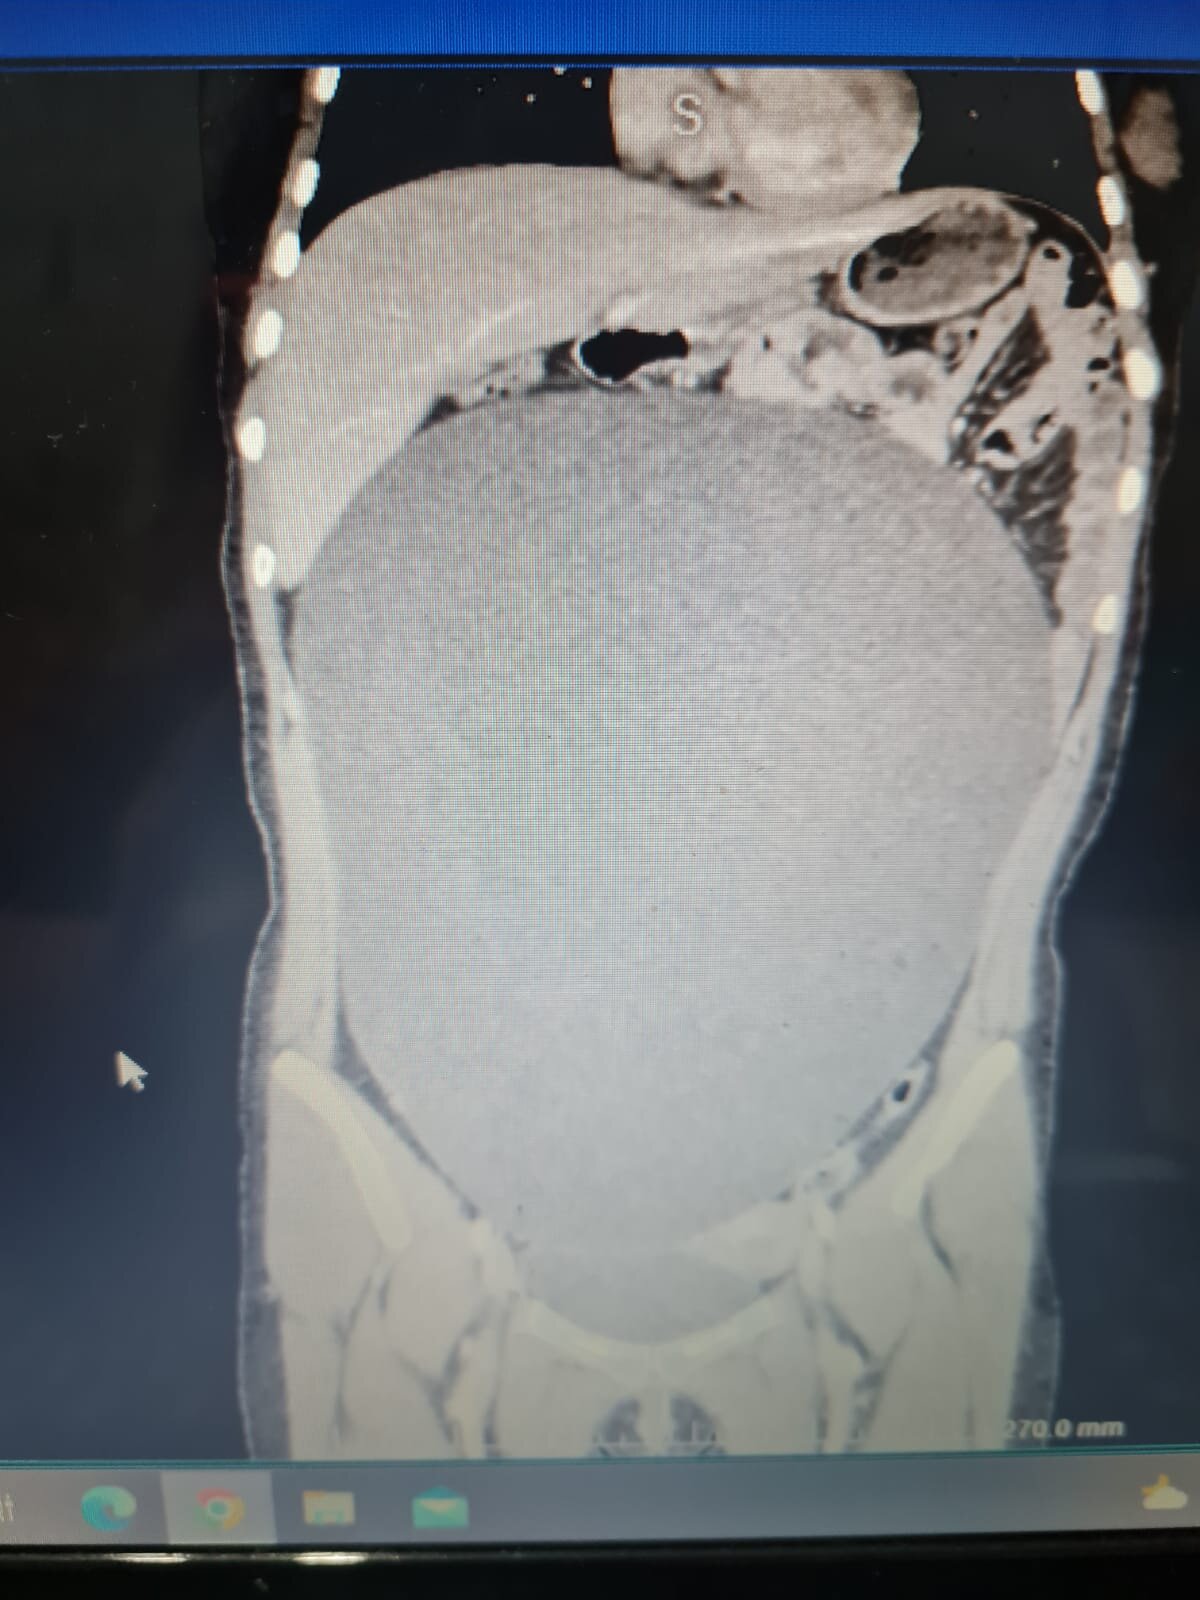

Aksaray'da halk otobüsünün çarpması sonucu hafif yaralanıp, hastaneye kaldırılan B.G.'nin (17) karnından, ameliyatla 60 santimetre büyüklüğünde, 7 kilo 800 gram ağırlığında kitle çıkartıldı. Ameliyatı yapan Çocuk Cerrahı Dr. Ayşe Betül Öztürk, ''Daha önce 26 santimlik bir kitle görmüştüm. Bu ise ondan daha büyük ve bütün karnını kaplamış şekilde, bütün organları itilmiş ve yer değiştirip küçülmüş ve yetirince gelişmemiş. Şu an da karın içinde ciddi bir boşluk oluştu. Kızımız da 7 kilo vermiş oldu. Durumu da gayet iyi" dedi.

Kaza, 25 Ağustos günü saat 18.30 sıralarında Taşpazar Mahallesi Atatürk Bulvarı'nda meydana geldi. Üniversiteye hazırlık kursundan çıkan B.G., yolun karşısına geçmek isterken halk otobüsü çarptı. Kazada yaralanan B.G., çağrılan ambulansla Aksaray Eğitim ve Araştırma Hastanesi'ne kaldırıldı. Tetkikler sırasında B.G.'nin karnında kitle tespit edildi. Ameliyata alınan B.G.'nin karnından 60 santimetre büyüklüğünde, 7 kilo 800 gram ağırlığında kitle çıkarıldı.

Kaza sonrası kızımın hastanede çekilen tomografi sonucunda karnındaki kist görülüyor. Doktoru tarafından acil ameliyata alınıyor ve başarılı bir ameliyat geçiriyor. Hiçbir belirtisi ve ağrısı yoktu. Biz de bu olaya çak şaşırdık. 7 kilonun üzerinde karnından bir kist çıktı. Biz de ne kadar süredir var bilmiyoruz. En ufak bir belirtisi olsa hemen doktora getirirdim. Hiçbir ağrısı ve sızısı yoktu kızımın. Halk otobüsü şoförü iyi ki kızıma çarpmış diyorum. Dün geceden bu yana otobüs şoförüne, kızıma iyi ki çarpmış diye dua ediyorum. Kaza sonrası da şoförden davacı olmadık. Kazayla ilgili kızımda şükür bir yaralanma yok. Doktoru Ayşe Betül ile konuşunca çok şaşırdım. Neden bu kadar acil bir ameliyat olması gerektiğini sordum. O da 'Karnındaki kist patlarsa kurtaramayabiliriz ve çok riskli, karnını tamamen kist sarmış' dedi. Başarılı bir ameliyatla kızım kurtuldu."

Ameliyatı gerçekleştiren Dr. Ayşe Betül Öztürk ise B.G.'nin karnındaki kitlenin doğuştan olduğunu ve giderek büyümesine rağmen hasta ve yakınları tarafından fark edilmediğini belirtti.

Kaza vakası sonrası böyle bir olayı ilk kez yaşadıklarını belirten Öztürk, ''Kızımız, bir trafik kazısı geçiriyor ve kendisine otobüs çarpması sonrası acil servise getiriyor.

Rutin kontrolleri yapılırken çekilen tomografisinde karın içerisinde büyük bir kitle olduğunu tespit edildi. Neredeyse bütün karnını kaplayan bir kitle nedeniyle hastayı hemen ameliyat aldık. Başarı bir ameliyatla yaklaşık 60 santimetre büyüklüğünde ve 7 kilo 800 gram ağırlığındaki kitleyi hiçbir sorun yaşamadan çıkardık.

Hastamızın şu an da durumu iyi ve besleniyor. Daha önce 26 santimetrelik bir kitle görmüştüm. Bu ise ondan daha büyük ve bütün karnını kaplamış şekilde, bütün organları itilmiş ve yer değiştirip küçülmüş ve yetirince gelişmemişti. Şu anda karın içinde ciddi bir boşluk oluştu. Kızımız da 7 kilo vermiş oldu.